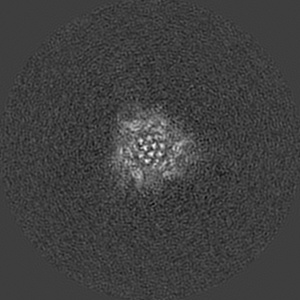

SARS-CoV-2 Wuhan Spike ectodomain in complex with NHP polyclonal antibody NVX-NHPSA5 (NVX-CoV2373/rS-Beta immunized)

Single-particle4.5 Å

Sample: SARS-CoV-2 Wuhan spike ectodomain in complex with NHP polyclonal antibody NVX-NHPSA5